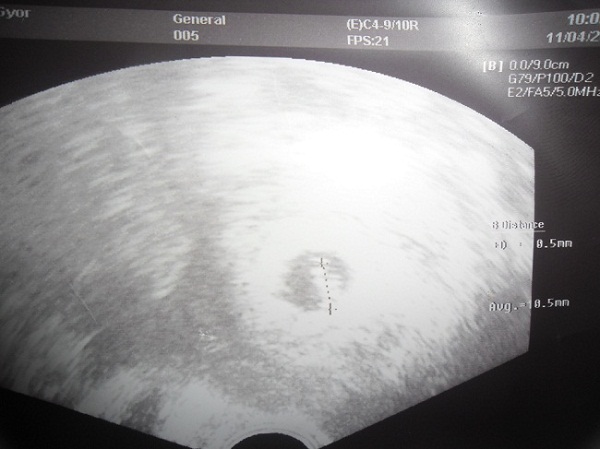

kiscucc, a vonal mögött bújkál a célkeresztben